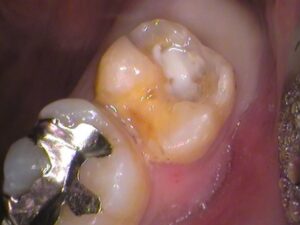

接着剤の汚れを取っていくと、

歯の中に白いものが。

セメントといってお薬で以前の治療で詰めてありました。

虫歯が大きく深い箇所に神経を保護するようにセメントが詰められます。

以前の古いセメントも削り取って歯の内部を確認します。

う蝕検知液という、虫歯を染色するお薬をつけてみると、

手前の歯との間の所が赤く染まっています。

レントゲン写真で銀歯の隙間が黒くなっていたところですね。

やはり虫歯がありました。